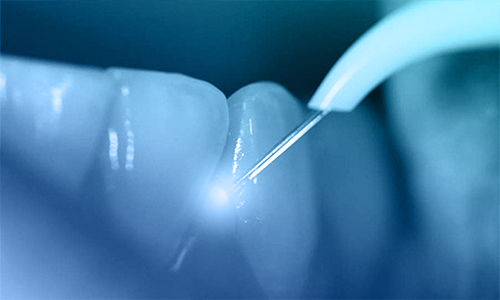

È considerato a ragione una delle più importanti scoperte del XX secolo. Il laser odontoiatrico è uno strumento medico che genera un raggio molto preciso di luce concentrata. Il raggio sterilizza la zona-bersaglio e allo stesso tempo coagula i vasi sanguigni riducendo di conseguenza il rischio di infezione e il sanguinamento. Risultato: le sedute dal dentista diventano molto più brevi e rilassanti, e nella maggior parte dei casi non vi è neppure bisogno di ricorrere all’anestesia. Alcune procedure possono essere eseguite in una frazione del tempo richiesto dallo stesso intervento senza laser, con evidenti benefici sulla durata del cosiddetto “tempo-sulla-poltrona”.

L’efficienza del laser è basata sui tassi di picco di assorbimento dei materiali contenuti nei tessuti-bersaglio (duri o molli) e di altro materiale dentale (per esempio, emoglobina, acqua, idrossiapatite, e così via) di lunghezze d’onda uniche. L’energia ottimale viene fornita con la minima emissione possibile, basata sulle caratteristiche di assorbimento uniche e precise delle singole lunghezze d’onda. Alcune di queste lunghezze hanno un’affinità con l’acqua e con le strutture pigmentate in rosso, ciò che le rende particolarmente efficaci per le procedure sui tessuti molli della cavità orale.